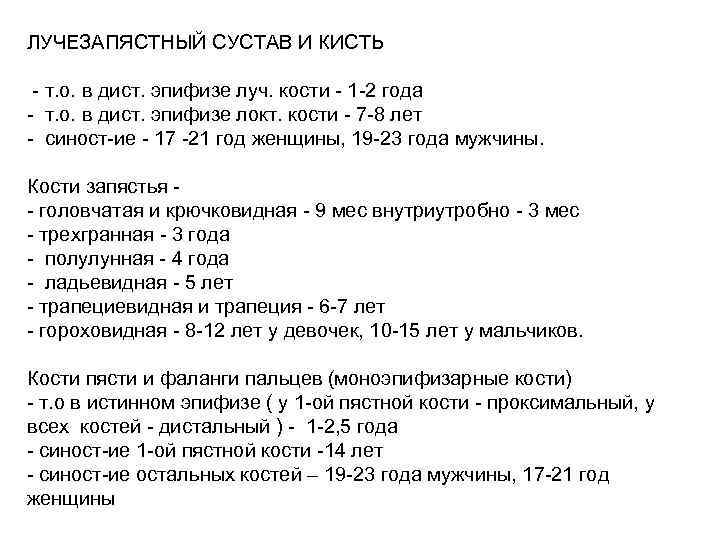

ЛУЧЕЗАПЯСТНЫЙ СУСТАВ И КИСТЬ - т. о. в дист. эпифизе луч. кости - 1 -2 года - т. о. в дист. эпифизе локт. кости - 7 -8 лет - синост-ие - 17 -21 год женщины, 19 -23 года мужчины. Кости запястья - - головчатая и крючковидная - 9 мес внутриутробно - 3 мес - трехгранная - 3 года - полулунная - 4 года - ладьевидная - 5 лет - трапециевидная и трапеция - 6 -7 лет - гороховидная - 8 -12 лет у девочек, 10 -15 лет у мальчиков. Кости пясти и фаланги пальцев (моноэпифизарные кости) - т. о в истинном эпифизе ( у 1 -ой пястной кости - проксимальный, у всех костей - дистальный ) - 1 -2, 5 года - синост-ие 1 -ой пястной кости -14 лет - синост-ие остальных костей – 19 -23 года мужчины, 17 -21 год женщины

ЛУЧЕЗАПЯСТНЫЙ СУСТАВ И КИСТЬ - т. о. в дист. эпифизе луч. кости - 1 -2 года - т. о. в дист. эпифизе локт. кости - 7 -8 лет - синост-ие - 17 -21 год женщины, 19 -23 года мужчины. Кости запястья - - головчатая и крючковидная - 9 мес внутриутробно - 3 мес - трехгранная - 3 года - полулунная - 4 года - ладьевидная - 5 лет - трапециевидная и трапеция - 6 -7 лет - гороховидная - 8 -12 лет у девочек, 10 -15 лет у мальчиков. Кости пясти и фаланги пальцев (моноэпифизарные кости) - т. о в истинном эпифизе ( у 1 -ой пястной кости - проксимальный, у всех костей - дистальный ) - 1 -2, 5 года - синост-ие 1 -ой пястной кости -14 лет - синост-ие остальных костей – 19 -23 года мужчины, 17 -21 год женщины